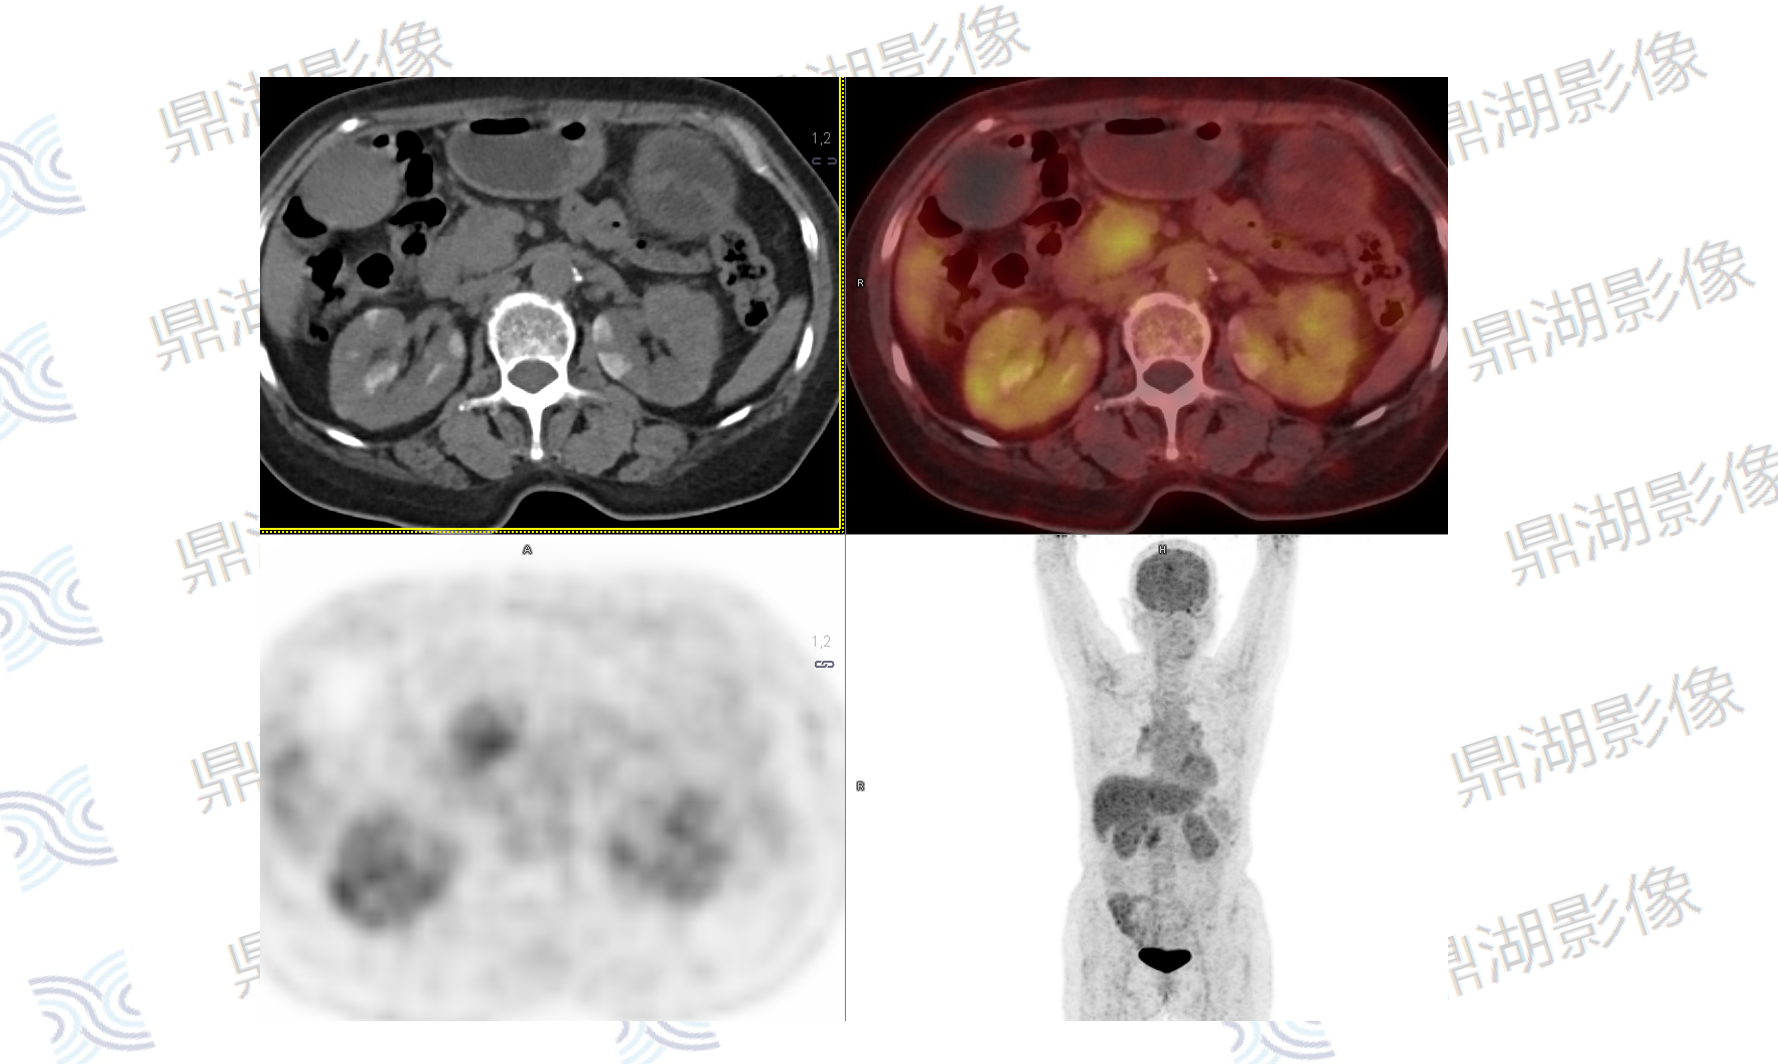

影像表现:胰腺钩突不规则软组织肿块,FDG摄取增高,SUVmax=4.3,病灶与邻近肠系膜上静脉分界不清,胰腺体尾部萎缩伴胰管扩张,胆总管及肝内胆管轻度扩张。